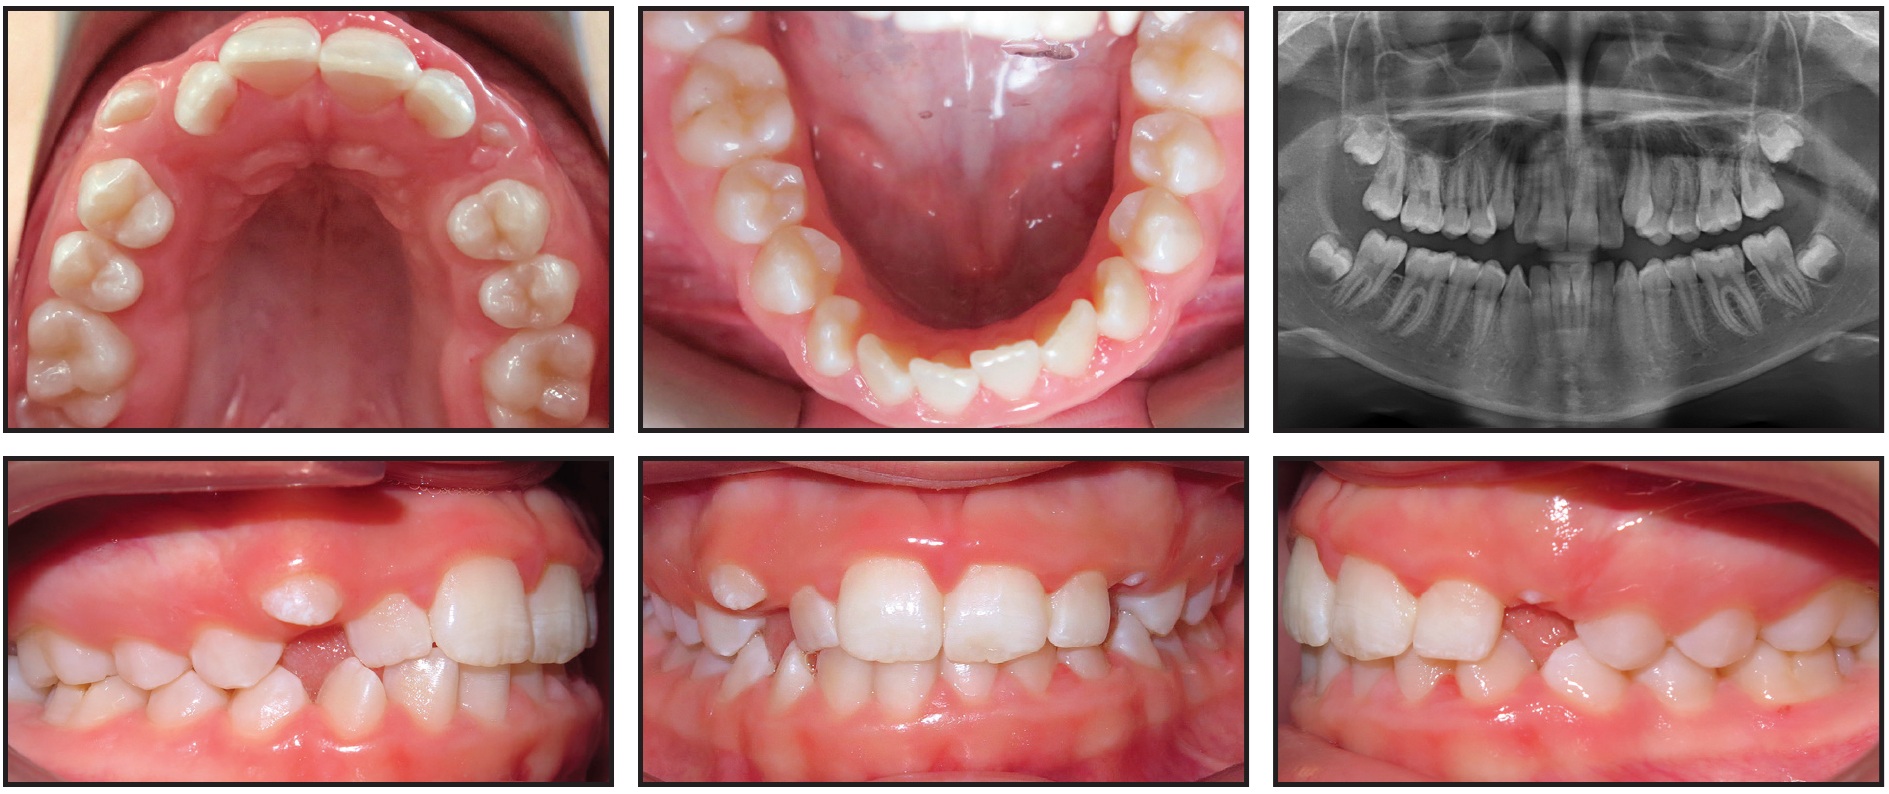

A 12-year-old female presented with the chief complaint that “my tooth is coming in a little high.” She had a straight profile with an obtuse mentolabial sulcus, symmetrical face, and thin lips, but she appeared tired because of dark infraorbital circles. The patient showed 100% incisal display on smiling, with 2.5mm of gingival display and wide buccal corridors. We noted a Class I molar relationship, moderate crowding in both arches, and a Class III skeletal relationship due to a prognathic mandible and a slightly low mandibular plane angle (Fig. 6). The patient had a 50% overbite, along with a 2mm maxillary anterior Bolton deficiency. There was inadequate space for the upper canines, which were beginning to erupt. The angulation of the canines was appropriate, however, and no resorption of the lateral incisors was observed.

Fig. 6 Case 2. 12-year-old female patient with Class III skeletal and Class I molar relationships, 50% overbite, and moderate crowding in both arches.

Panoramic radiography revealed enlarged nasal turbinates; all permanent teeth were present, and the third molar buds were developing. Cephalometric analysis indicated retroclined mandibular incisors, slightly proclined maxillary incisors, and a cervical vertebral maturation stage 2.24